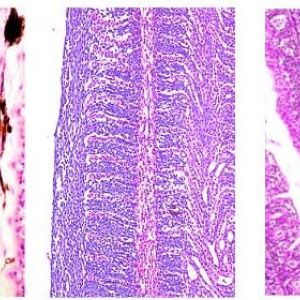

Fish Histopathology 2025: A Focus on Gills

Fish Histopathology 2025: A Focus on Gills The fish histopathology workshop will be held on Sunday 31 August 2025, before the actual conference.